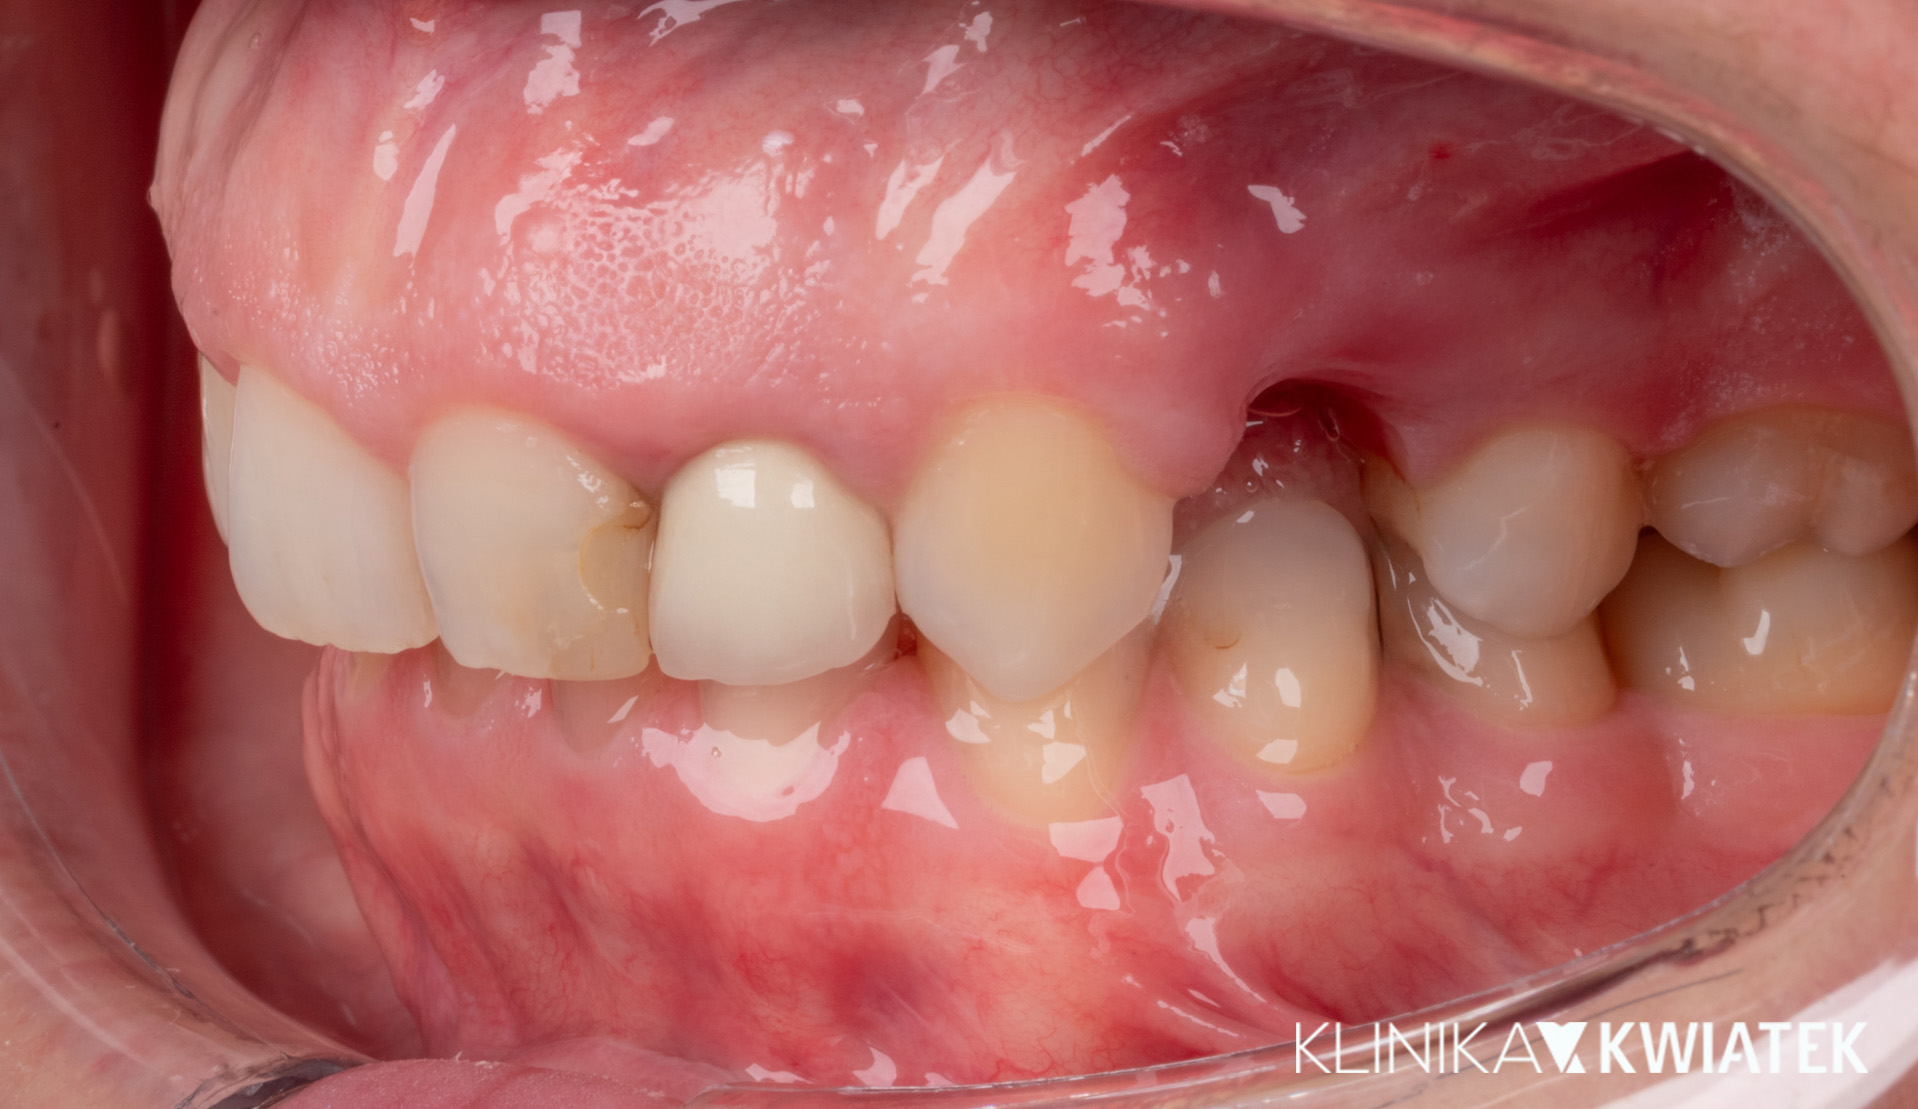

Kliniczna precyzja i estetyka – jak przywróciliśmy funkcję i piękno uśmiechu

Pacjentka zgłosiła się z wadą zgryzu, licznymi ubytkami i utraconymi zębami trzonowymi, co powodowało trudności w żuciu i estetyczne niezadowolenie. Leczenie obejmowało ekstrakcje, ortodoncję, implantację oraz kompleksową rekonstrukcję protetyczną. Po kilkunastu miesiącach terapii Pacjentka odzyskała pełną funkcję zgryzu i piękny, harmonijny uśmiech.